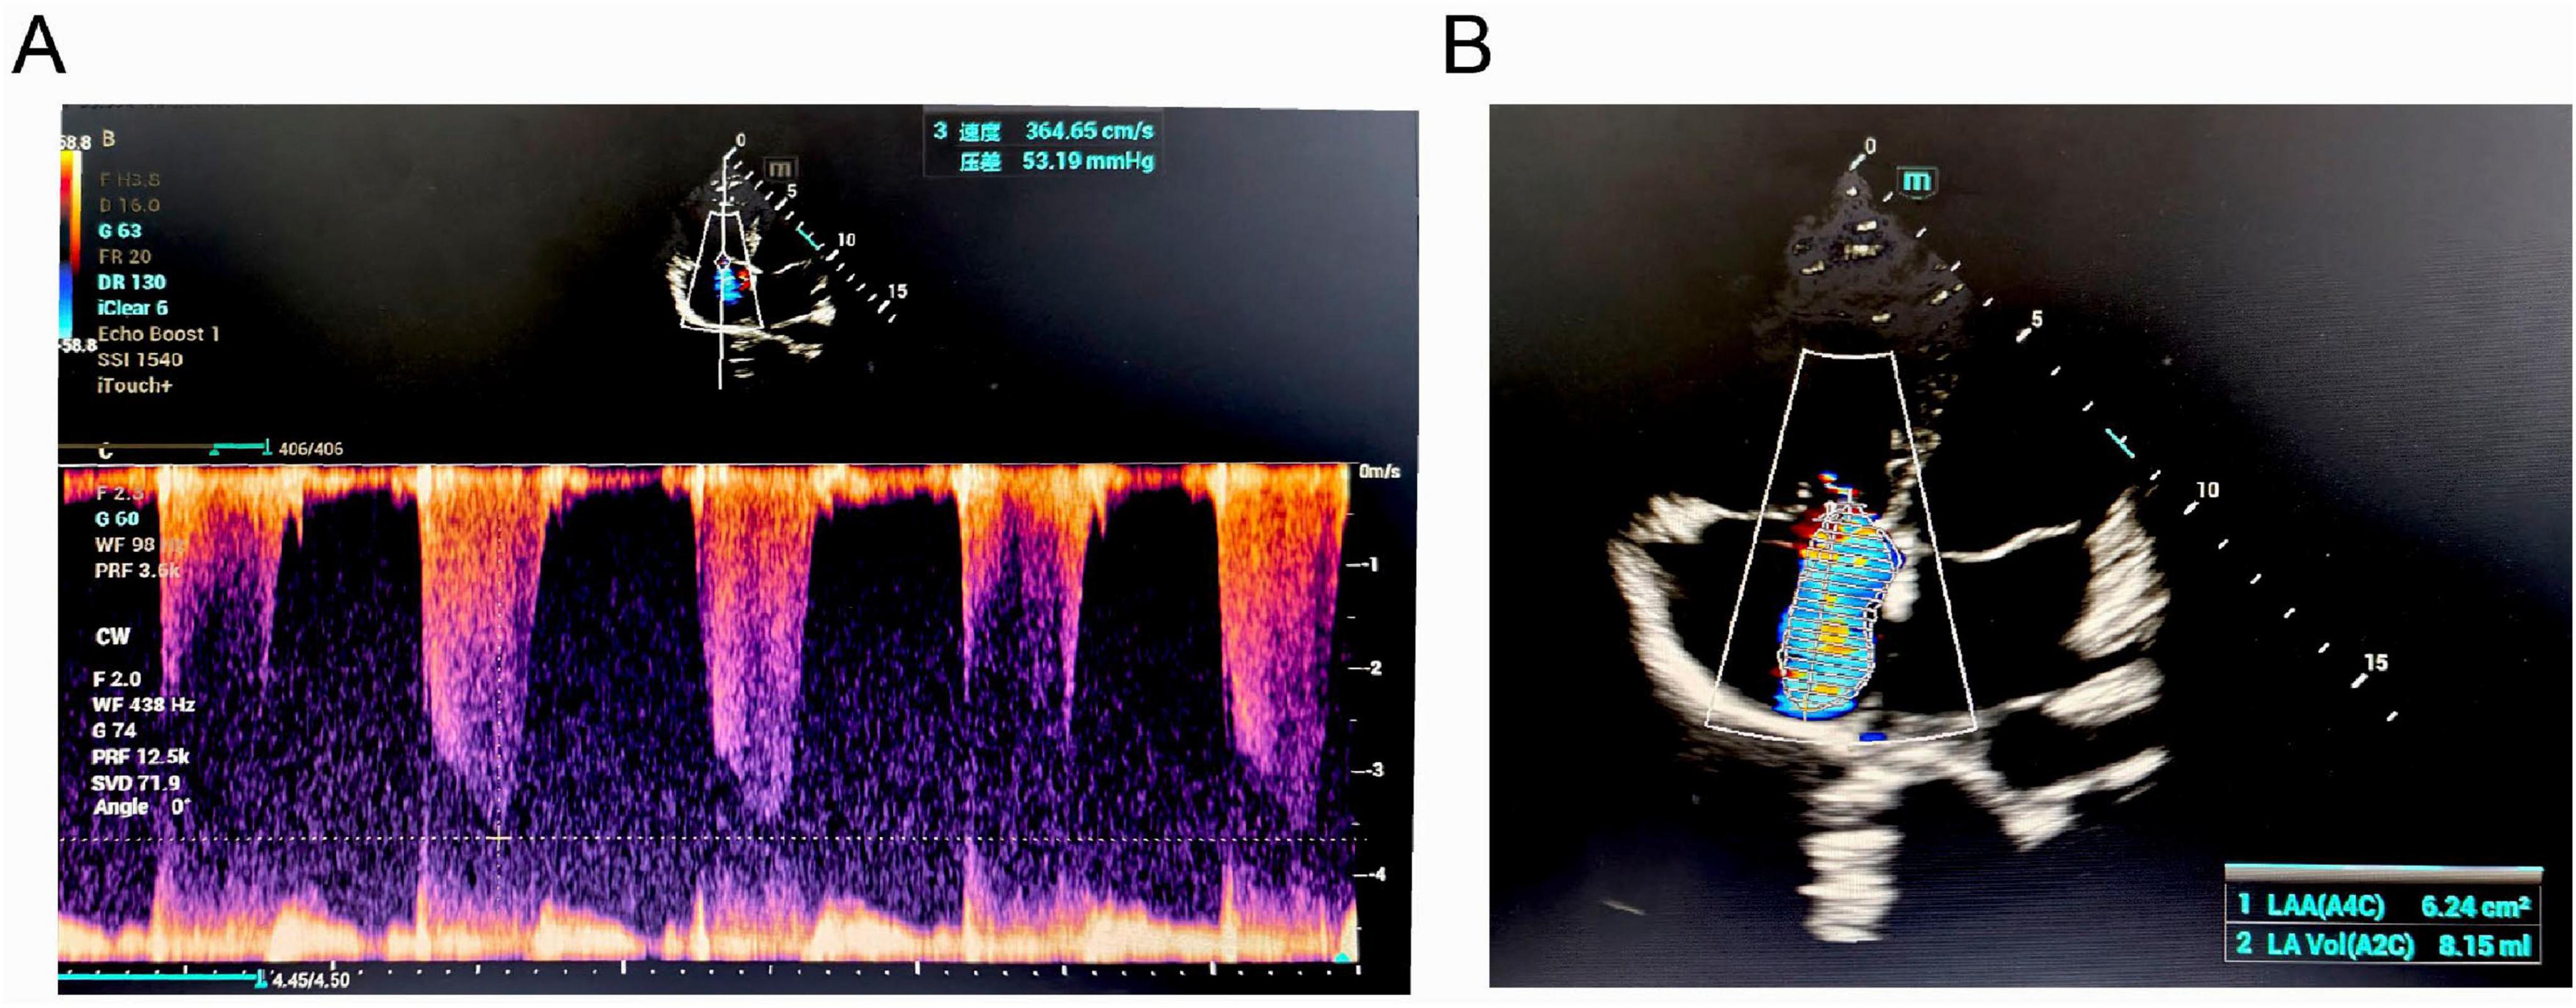

Background: The high-altitude environment characterized by hypobaric hypoxia can cause significant damage to the cardiovascular system, particularly vascular endothelial function, and is a significant trigger for acute and chronic mountain sickness. High-altitude pulmonary hypertension (HAPH) is a serious complication induced by prolonged exposure to high altitude, characterized by abnormally elevated pulmonary artery pressure and increased right heart load, which can progress to right heart failure and be life-threatening. This article aims to enhance clinicians' understanding of this disease through two cases of HAPH in young males. Case Description: Case 1 was a 21-year-old male who developed progressively worsening chest pain, shortness of breath, and amaurosis fugax after living at an altitude of 4800 meters for 4 months. Case 2 was a 20-year-old male who experienced exertional dyspnea accompanied by amaurosis fugax and a brief loss of consciousness after 18 months of residence at 4300 meters. Both patients were previously healthy with normal cardiopulmonary function before moving to high altitude. Physical examination upon presentation revealed significant hypoxemia (oxygen saturation 80% and 82% on room air, respectively). Echocardiography in both cases clearly demonstrated right atrial and right ventricular enlargement, moderate tricuspid regurgitation, with estimated systolic pulmonary artery pressures (sPAP) as high as 55 mmHg and 56 mmHg, respectively. Chest CT confirmed right heart enlargement and main pulmonary artery dilation. After systematic evaluation excluded other etiologies, HAPH was diagnosed. Discussion: The core pathophysiology of HAPH is hypoxia-induced pulmonary vasoconstriction and remodeling. These cases demonstrate that even for young, healthy individuals, prolonged exposure to extremely high altitudes can lead to severe pulmonary hypertension and right ventricular dysfunction. Diagnosis requires a combination of high-altitude exposure history, clinical symptoms, evidence of hypoxemia, and echocardiographic findings. The most fundamental treatment for diagnosed HAPH patients is removal from the high-altitude hypoxic environment, making early recognition and intervention crucial. Conclusion: The high-altitude environment poses a serious threat to the cardiovascular systems of susceptible individuals. For patients with a history of high-altitude residence who present with relevant symptoms, clinicians should maintain a high index of suspicion for HAPH and conduct timely screening and diagnosis to prevent adverse outcomes.